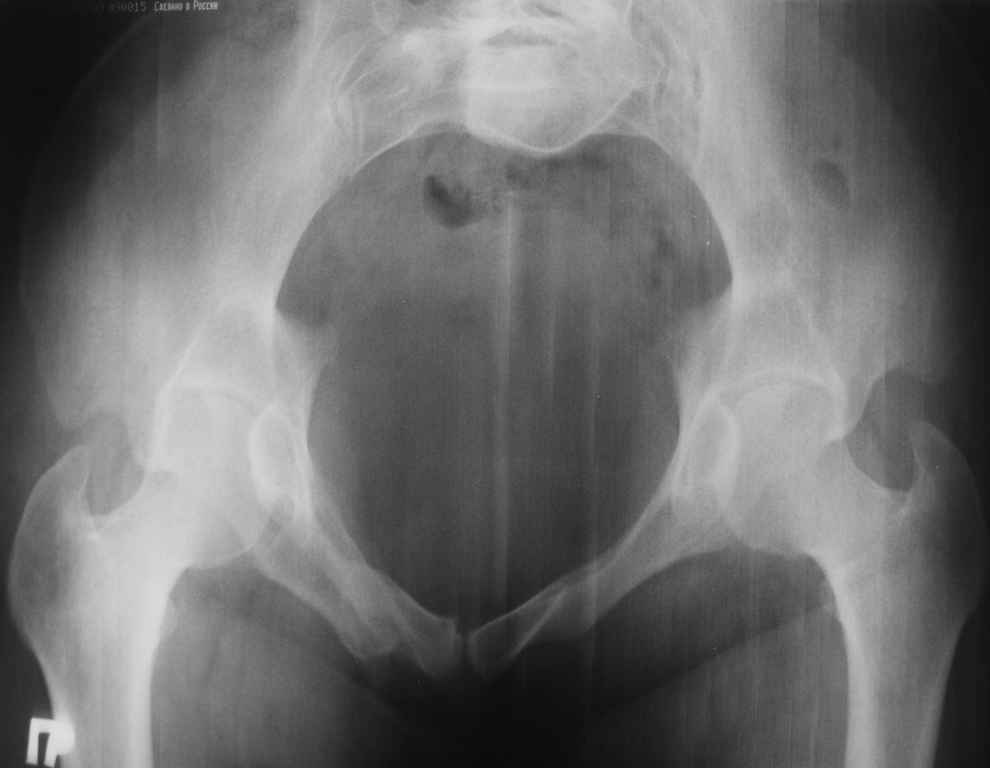

13/03/03 |  13/03/03 |  13/03/03 |  15/09/06 |  15/09/06 |  07/03/07 |  07/03/07 |  19/12/06 | К нам в клинику поступила пациентка 30 лет с диагнозом: Постравматическая ротационная стабильная деформация тазового кольца. Относительное укорочение левой н\конечности на 1 см. Левосторонний компенсаторный сколиоз 2 ст. Болевой синдром. травма автодорожная в январе 2003г. Пассажирка переднего сидения ваз 2109. лечились положением по Волковичу. С марта 2003 года жалуется на боли в тазу, ппояснице усиливающиеся при движении.В настоящее время жалобы на боли в области крестца, КПС больше слева, в пояснично-крестцовом отделе позвоночника. неприятные ощущения, щелчок при выпрямлении правого тазобедренного сустава из положения полного сгибания. боли в тазу появляются при ходьбе ч\з 100 м, так же при вставании из положения сидя, после сидения в течении 2-3 часов. при ходьбе более 100 м появпяется зябкость стоп больше справа. ходит при помощи трости в правой или в левой руке. без трости боли появляются сразу после начала ходьбы. пальпация болезненна в паравертебральных точках средне-грудного и пояснично-крестцового отделов позвоночника, КПС с обеих сторон. Объем движений в тазобедренных суставах полный.правый КПС заблокирован. симптомы натяжения с обеих сторон отрицательны.С 2003г. лечится консервативно, получала ЛФК, массаж, физиолечение - без эффекта. в 2005г. лечилась в санатории с ортопедическим уклоном, получала плавание в минеральной воде, магнитотерапия, массаж, ЛФК. отмечала умеренное улучшение в течении 2 недель.Вопросы:надо ли оперировать, т.е. устранять относительное укорочение левой н\конечности и как?Если не оперировать, то как лечить консервативно?Р-граммы, КТ прилогаются.

Уважаемый Алексей. Описанные Вами клинические проявления указывают на нестабильность левого крестцово-подвздошного сочленения. Такие больные встречаются не редко (за последние 6мес.в нашей клинике оперировано 3 больных со сроками давности от 6мес. до 1 года). К сожалению рентгенологически их трудно обьективизировать. На КТ это проявляется артрозом и костными разрастаниями КПС. В Вашем случае рентгенограммы и представленные томограммы ничего не дали. Можно попробовать посмотреть связочный аппарат КПС на МРТ хотя не уверен что Вы получите окончательный ответ. Если Вы будете убеждены в этом диагнозе то выход один костно-пластический артродез левого крестцово-подвздошного сочленения с фиксацией канюлированными шурупами. Заманчиво конечно и устранить ротационное смещение половины таза, но это на Ваше усмотрение.

почему она должна возникнуть? Сломан вроде крестец, хотелось бы посмотреть функциональные снимки таза.

Уважаемый Максим. Снимки от 7.03.07 и есть функциональные, т.е. стоя на правой, и левой ноге.